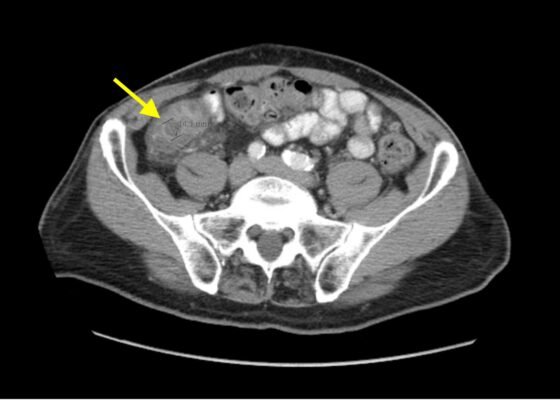

Imaging Findings of Small Bowel – Diverticulitis: A Case Report

DOI: https://doi.org/10.21980/J8F078Bedside ultrasound was performed and showed thickened bowel wall (orange marker), fat enhancement (green marker), and phlegmonous structure with central echogenicity (yellow marker). Imaging of the abdomen and pelvis with CT showed marked wall thickening and inflammatory change involving a 7.0cm segment of the distal/terminal ileum suspicious for severe ileitis with phlegmon and microabscess on the coronal image (yellow arrow). Additonally, the transverse images show a small rim-enhancing focus within this region of inflammation measuring up to 1.4cm which could represent microabscess (yellow arrow). Diagnosis of diverticulitis by ultrasound is made by identifying the following findings: colon wall thicker than 5mm, fat enhancement, evidence of abscess, visualized diverticuli, air artifacts suggesting diverticuli, and tenderness with compression of the probe.6 Diagnosis of diverticulitis by CT is made by identifying the following findings: colonic wall thickening, pericolic fat stranding, abscess formation and enhancement of the colonic wall. Often, these signs are associated with an identifiable inflamed diverticulum.7